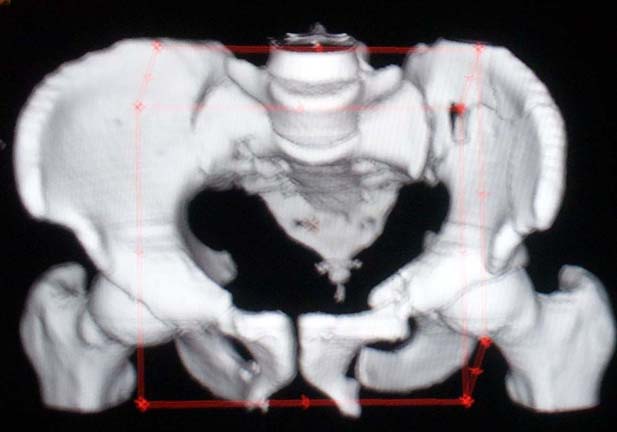

PS- I enclose two images from a closed reduction and percutaneous fixation procedure in a similar pattern...but our patient had a much smaller intact/stable posterior iliac "crescent" segment, so iliosacral screws were very effective in his particular pattern.

The iliac fracture with associated sacroiliac anterior disruption (some call this a "crescent fracture-dislocation") might allow manipulative reduction and percutaneous iliosacral screw fixation....it's difficult to know if an iliosacral screw would work without a routine 2-D CT to examine. It might not be possible for this specific fracture because of it's location. The screw must connect the unstable iliac component to the sacrum...some have used iliosacral screws for these "more anterior" iliac fracture patterns, but the iliosacral screw is mistakenly inserted through the stable iliac posterior (crescent fragment) component into the sacrum...that screw doesn't accomplish much....don't do that!

As far as open techniques, this injury pattern also can be reduced and stabilized using the lateral "window" of an ilioinguinal exposure. This approach would save time since both the Pfannenstiel and lateral window can be performed with the patient supine. You can even open both, then manipulate the ramus and iliac-SI injuries together.